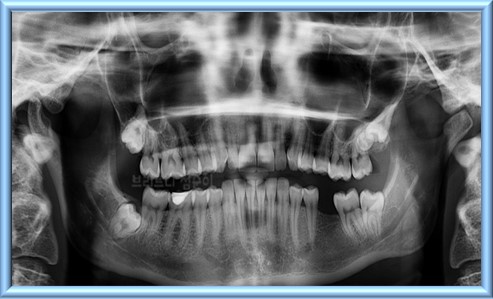

교정 치료는 초기 상담 및 자세한 검진이 필요하다. 초기 상담에서는 환자의 치아 상태를 확인하고 교정 계획을 수립한다. 이때 엑스레이, CT 스캔, 치과 모형 등 다양한 검사를 한다. 초기 상담 및 자세한 검진 비용은 10만 원에서 50만 원 사이이며, 일부 병원에서는 무료로 제공한다.